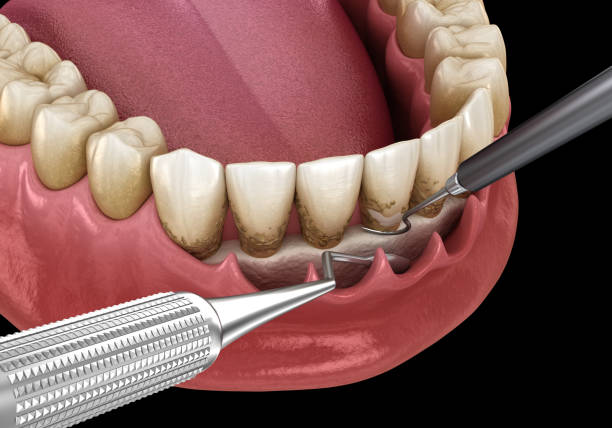

la terapia causale è la prima tappa e si fonda sull’ottimizzazione dell’igiene orale domiciliare, sulla rimozione non chirurgica dei microbi dalle superfici radicolari (levigatura radicolare).